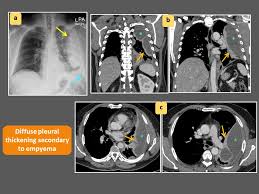

Pleural effusions are characterized on ct by attenuation values between those of water (0 hounsfield units hu) and soft tissue (approximately 100 hu), typically in the order of 10 to 20 hu. Pocus demonstrated a large right sided loculated pleural effusion with associated septations and surrounding consolidation suggestive of a parapneumonic effusion. This is for educational purpose. A right thoracentesis was performed, and on seeing the biochemistry results, the left side was also punctured. Loculated effusion • pleural effusions can loculate as a result of adhesions Loculated pleural effusions can occur in isolation and, as in this case, be idiopathic. Pet and mri scans provide even further detail and may be used to differentiate pleural thickening from malignant mesothelioma. 1) to see if loculated or free fluid 2) to determine if enough volume to do a thoracocentesis (volume required is greater than 1cm)

Loculated pleural fluid in a fissure can mimic a pulmonary mass and hence is sometimes referred to as a pseudomass or pseudotumor. Pleural effusion predominantly presents with breathlessness, but cough and pleuritic chest pain can be a feature. Blunting of the lateral costophrenic angle usually requires about 175 ml but may take as much as 500 ml. However, if the fluid has accumulated in this cavity, an opacity in this space is visible. Pet and mri scans provide even further detail and may be used to differentiate pleural thickening from malignant mesothelioma. Pocus demonstrated a large right sided loculated pleural effusion with associated septations and surrounding consolidation suggestive of a parapneumonic effusion. Pleural effusion with a missing breast suggesting resection for cancer : 1) to see if loculated or free fluid 2) to determine if enough volume to do a thoracocentesis (volume required is greater than 1cm) A pleural effusion is a collection of fluid in the space between your chest wall and lungs. Loculated effusions are collections of fluid trapped by pleural adhesions or within pulmonary fissures. 02, 2015 37,660 views prepared by medical student of nepal. Loculated pleural effusions can occur in isolation and, as in this case, be idiopathic. An ultrasound, chest computed tomogr.

Pleural effusions are characterized on ct by attenuation values between those of water (0 hounsfield units hu) and soft tissue (approximately 100 hu), typically in the order of 10 to 20 hu.

Pleural effusions are characterized on ct by attenuation values between those of water (0 hounsfield units hu) and soft tissue (approximately 100 hu), typically in the order of 10 to 20 hu. Pleural effusion symptoms are still in x ray even after 6 month treatment. A pleural effusion is a collection of fluid in the space between your chest wall and lungs. Loculated pleural effusion masquerading as mediastinal tumour had been reported but pleural effusion that conformed to the contour of a lung lobe is rare (5,6). If the fluid cannot be drained, the lungs aren't able to expand and oxygenate the blood sufficiently. The aetiology of the pleural effusion determines other signs and symptoms. Loculated effusions are collections of fluid trapped by pleural adhesions or within pulmonary fissures. Pleural effusion with apical infiltrates: A ct scan, which is also used to diagnose asbestosis and pleural plaques, can confirm the condition earlier. Pleural effusion is when fluid fills this gap and separates the lungs from the chest wall. Fibrotic scar tissue may form in the pleural cavity (called loculation), preventing effective drainage of the fluid. 02, 2015 37,660 views prepared by medical student of nepal. Erleben sie zuverlässige pharmazeutische beratung.

Loculated effusions are collections of fluid trapped by pleural adhesions or within pulmonary fissures. Pleural effusion with a missing breast suggesting resection for cancer : Pocus demonstrated a large right sided loculated pleural effusion with associated septations and surrounding consolidation suggestive of a parapneumonic effusion. The excess accumulation of fluid can usually be seen on these images. Tried, tested, trusted and affordable for all qpcr needs. The hilum is visible through the mass. An ultrasound, chest computed tomogr. If the fluid cannot be drained, the lungs aren't able to expand and oxygenate the blood sufficiently. Chest radiographs are the most commonly used examination to assess for the presence of a pleural effusion; Pleural effusions are characterized on ct by attenuation values between those of water (0 hounsfield units hu) and soft tissue (approximately 100 hu), typically in the order of 10 to 20 hu. Dome shaped opacity projecting into the lung noted tracking along the cp angle and lateral chest wall suggestive of loculated pleural effusion, however the possibility of empyema can not be ruled out completely. Fibrotic scar tissue may form in the pleural cavity (called loculation), preventing effective drainage of the fluid. Treatment may fail if the catheter is not placed optimally within the loculation or if the fluid is hemorrhagic or fibrinous.